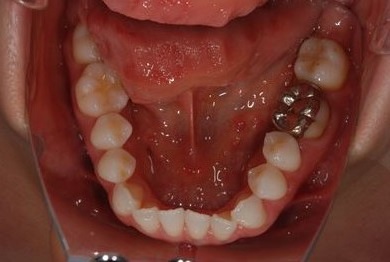

性別/年齢 女性 / 32歳

主訴 銀歯を白い歯にしたい。

治療方針 セラミック治療にて、審美的回復を行う。

治療内容 ハイブリッドセラミッククラウン1本、ハイブリッドセラミックインレー1本

治療前